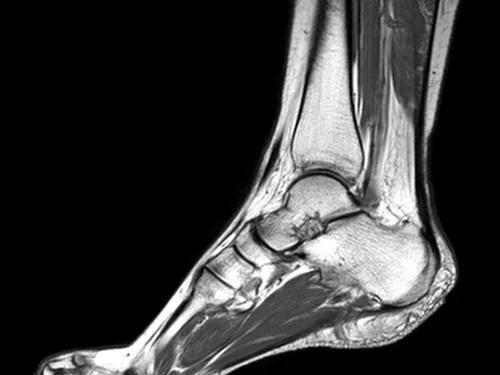

This reporting course (30 cases/6 modules) provides a solid foundation in the complex anatomy of the ankle. Selected MRI cases will highlight the most relevant pathologies. The course will teach a structured approach to reporting, following a list of anatomical areas to help distinguish between normal and abnormal changes in various anatomical structures.